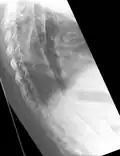

The earliest changes demonstrable by plain X-ray shows erosions and sclerosis in sacroiliac joints. Progression of the erosions leads to widening of the joint space and bony sclerosis. X-ray spine can reveal squaring of vertebrae with bony spur formation called syndesmophyte. This causes the bamboo spine appearance. A drawback of X-ray diagnosis is the signs and symptoms of AS have usually been established as long as 7–10 years prior to X-ray-evident changes occurring on a plain film X-ray, which means a delay of as long as 10 years before adequate therapies can be introduced.[25]

-

Lateral X-ray of the mid back in ankylosing spondylitis

Lateral X-ray of the mid back in ankylosing spondylitis -

X-ray showing bamboo spine in a person with ankylosing spondylitis

X-ray showing bamboo spine in a person with ankylosing spondylitis -